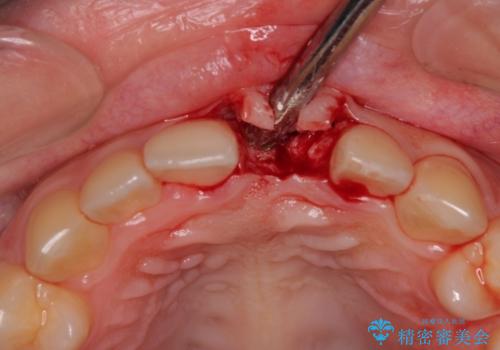

- 前歯のインプラント治療を希望して来院された患者様です。

小学生の時に前歯を殴打したとのことで、歯根が吸収してしまい、抜歯が必要と判断されました。

抜歯、インプラント埋入、仮歯の装着が同時に可能な1DAYインプラントを行いたいところでしたが、吸収による歯肉の炎症が著しいため、抜歯後に炎症が治まるまで待機し、極力早期にインプラント埋入を行うこととしました。